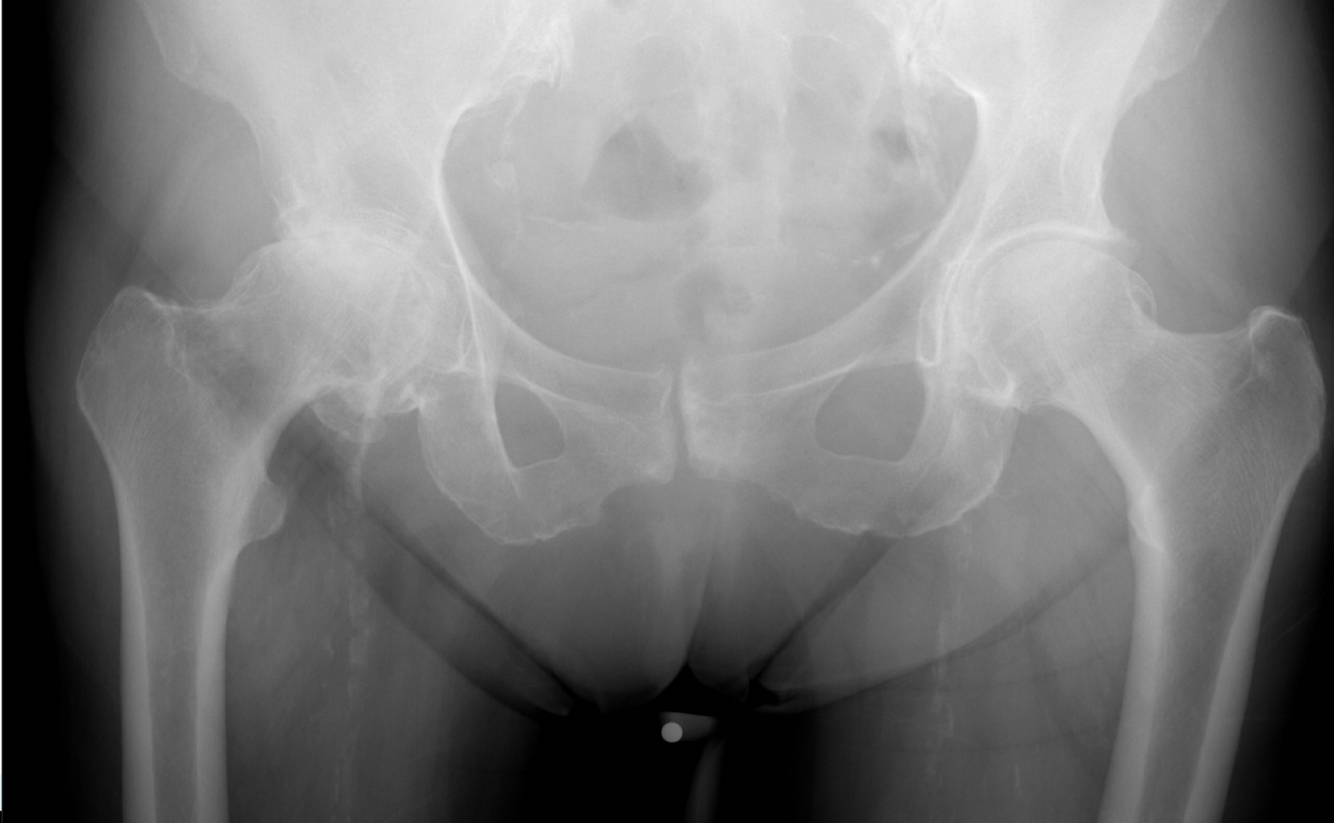

15

Q

Quels sont les 4 signes radiologiques de l’arthrose?

A

1. Le pincement articulaire;

2. La sclérose sous-chondrale;

3. Les ostéophytes;

4. Les kystes sous-chondraux

kystes sous-chondraux plus rares